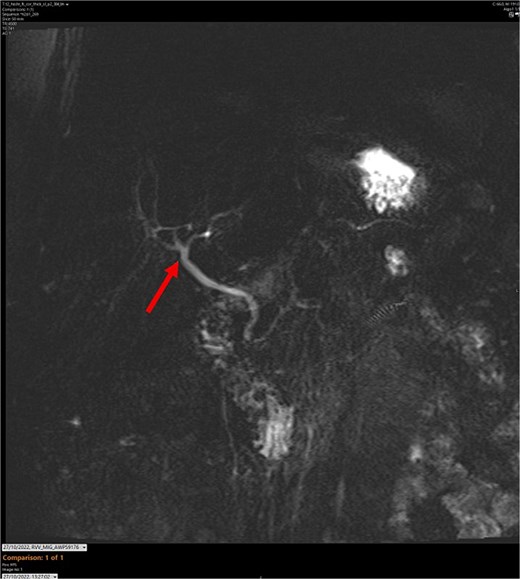

T2-weighted MRCP scan in coronal view. The arrow points to where we expect the gallbladder to be seen, but it cannot be visualized on the scan.